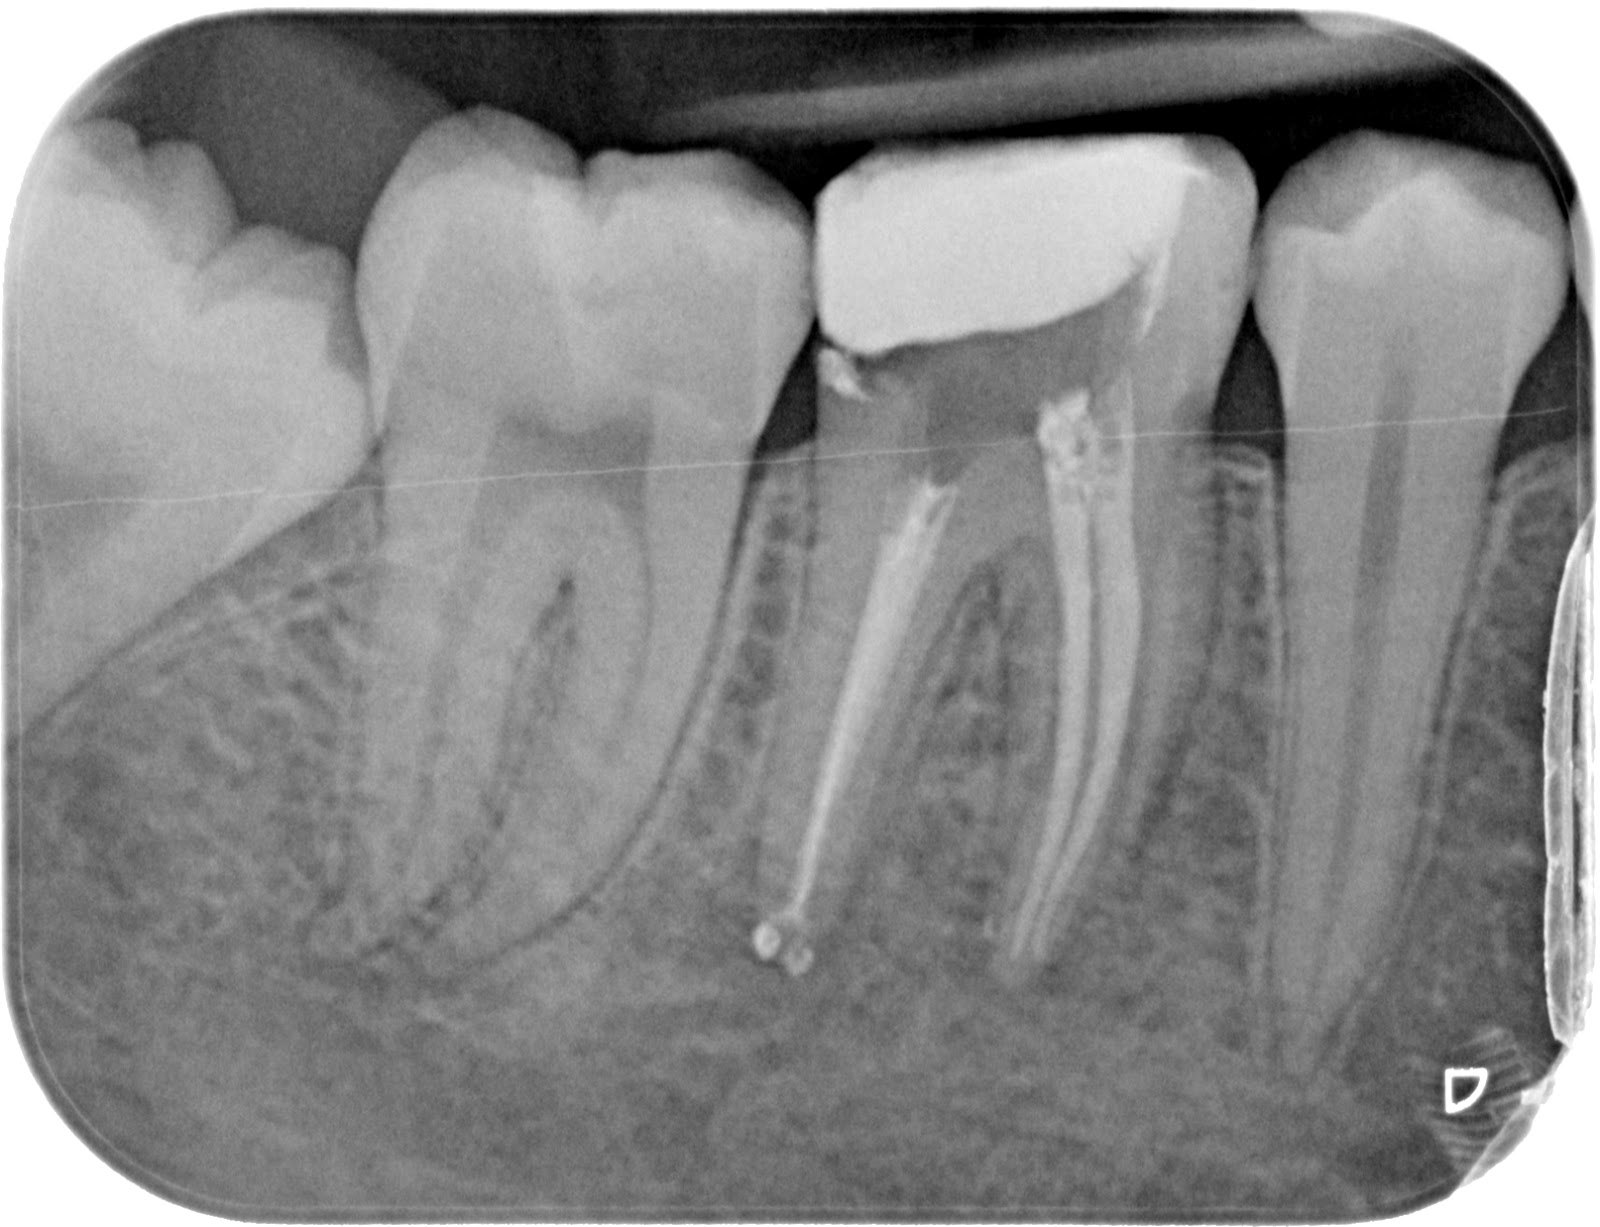

A la exploración intraoral observamos

una caries extensa en el diente 46. Los adyacentes no cursaban de ninguna

patología. Le realizamos las pruebas correspondientes y anotamos: Vitalidad

positiva aumentada y positiva normal en los adyacentes, percusión negativa en

todo el cuarto cuadrante, palpación negativa en todo el cuadrante y sondaje

fisiológico en el mismo. La movilidad era de 0. En la prueba radiológica

observamos que la caries ocluso-mesial del 46 se extiende hasta pulpa. Además

no presentaba ni calcificaciones, ni reabsorciones, ni fractura de la corona o

raíz, el espacio periodontal estaba intacto, ni tampoco existían imágenes

periapicales.

Conducto MV= 21 mm con referencia en

cúspide mesiovestibular.

Conducto ML= 21 mm con referencia en

cúspide mesiolingual.

Conducto DV= 21,5 mm con referencia en

cúspide distovestibular.

Conducto DL= 21 mm con referencia en

cúspide distolingual.